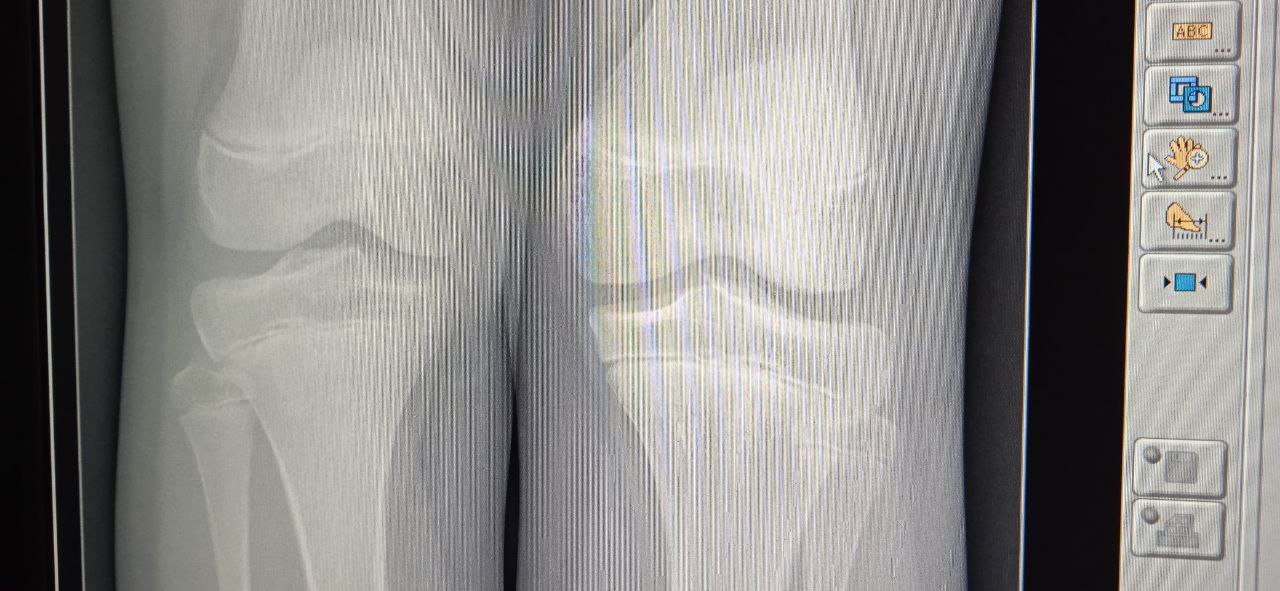

Уважаемые коллеги! Помогите, пожалуйста! Шляттер?

Теже ножки, обе в прямой

10 лет, жалобы на боли в правом коленном суставе

Фрагментации не вижу.

Не он???

Я и сам фрагментации не вижу, но, как мне кажется, есть тот самый "хоботок"

Это норма. Читаем Садофьеву.